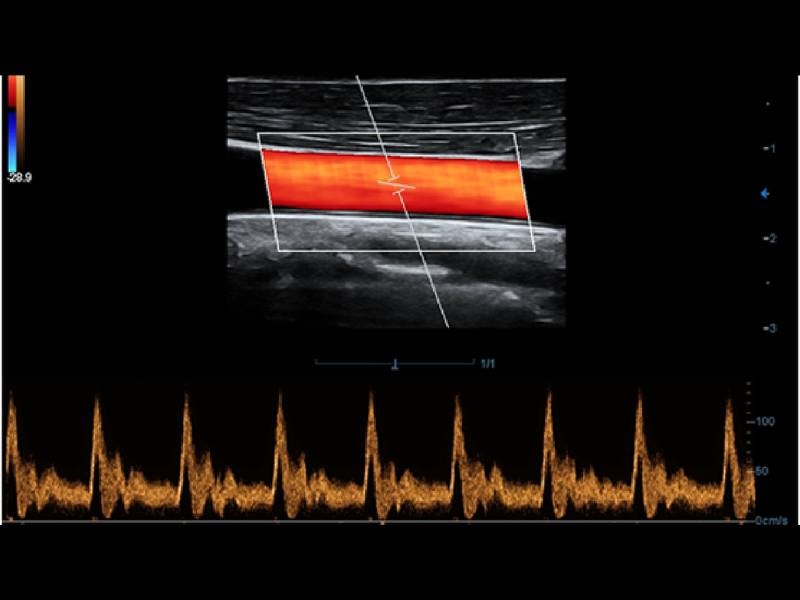

O Smart Track proporciona uma otimização rápida e inteligente das imagens vasculares com apenas um toque. Ele pode otimizar o espectro de cor, energia e PW por meio de rastreamento automático e reduz as etapas demoradas. Portanto, o fluxo de trabalho do exame vascular é simplificado por meio de uma visão ideal.